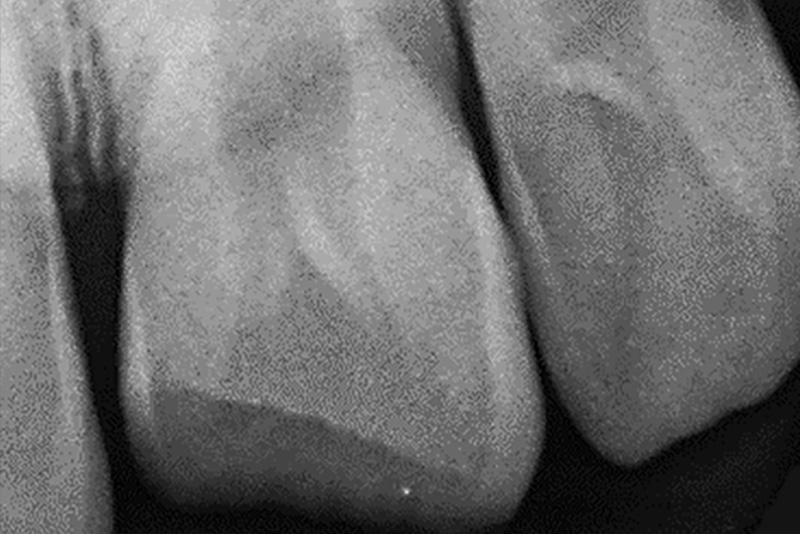

Mit seinem Vater als Begleitperson stellte sich der elfjährige Patient im August 2021 mit einer Frontzahnfraktur (21) vor, unmittelbar nach einem Freizeitunfall beim Stunt-Scooter- Fahren. Die Einzelzahnaufnahme ergab eine Schmelz-/ Kronenfraktur mit einer punktförmigen Pulpaeröffnung und fraglicher Vitalität. Darüber war eine apikale hypoden-se Struktur am Zahn 21 und 22 ersichtlich. Intraoral wurde eine Infraposition von Zahn 21 um 0,5 bis 1mm gegenüber den Nachbarzähnen festgestellt, dazu eine erhöhte Mobi-lität von 21,22,31,32 mit Lockerungsgrad 1, Perkussions-empfindlichkeit von 21 (++). Das Zungenbändchen war minimal eingerissen und in der Unterkieferfront zeigten sich Hypersensibiliäten. An der Unterlippe waren Riss- und Quetschwunden medial Regio 11,21/31,41 zu sehen. Das mitgebrachte Zahnfragment wurde zur schnellstmöglichen Remineralisation in eine Zahnrettungsbox gelegt.

Die behandelnde Zahnärztin klärte ein eventuell vorliegen-des Schädel-Hirn-Trauma sowie der Tetanusschutz ab. Es folgten eine ausführliche Anamnese und Diagnostik; unter anderem mit Hilfe von Röntgenbildern sowie eines Befund-bogens für Frontzahntraumata. Dazu gehörte auch eine Vitalitätsprüfung aller Frontzähne.